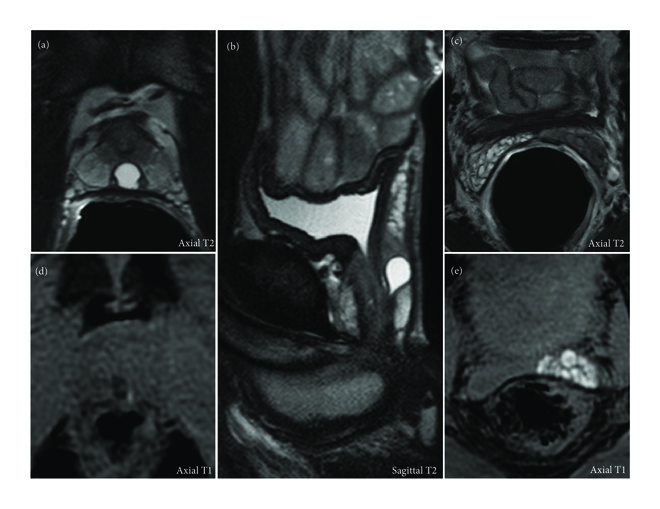

Further investigations were pursued by transrectal ultrasound (TRUS) that showed an infracentimetric anechoic lesion located posteriorly to the prostatic urethra. This finding in association with the high frequency of occurrence of hematospermia justified the indication to a complementary magnetic resonance imaging (MRI). The exam was performed in a high-field 3-tesla unit with an endorectal coil. MRI confirmed the cystic nature of the prostatic lesion as a well-delimited median intraprostatic structure, hyperintense T2 and hypointense T1 (Figure 1, Panels (a), (b), and (d)). The pear-shaped intraprostatic cyst measured 7.5 × 8.5 mm in the axial plan and 12 mm in the cranial-caudal axis. The examination also depicted stigmata of hematospermia in the left ejaculatory duct and seminal vesicle such as low signal intensity on T2-weighted images (Panels (a) and (c)) and spontaneous high signal intensity on T1-weighted images (Panels (d) and (e)). A definite classification of this midline cyst would have required a minimally invasive approach with transrectal ultrasonography-guided opacification and dye-injection study [4], but the patient refused further investigations. Based on the young age of the patient and the size of the lesion, we concluded to a prostatic utricle cyst. The lesion being a solitary finding without significant clinical symptoms but occasional episodes of hematospermia, the patient was reassured and a conservative approach was chosen. After excluding all other causes, we retained this midline cyst as the most likely cause of hematospermia even in the absence of intralesional hemorrhage.